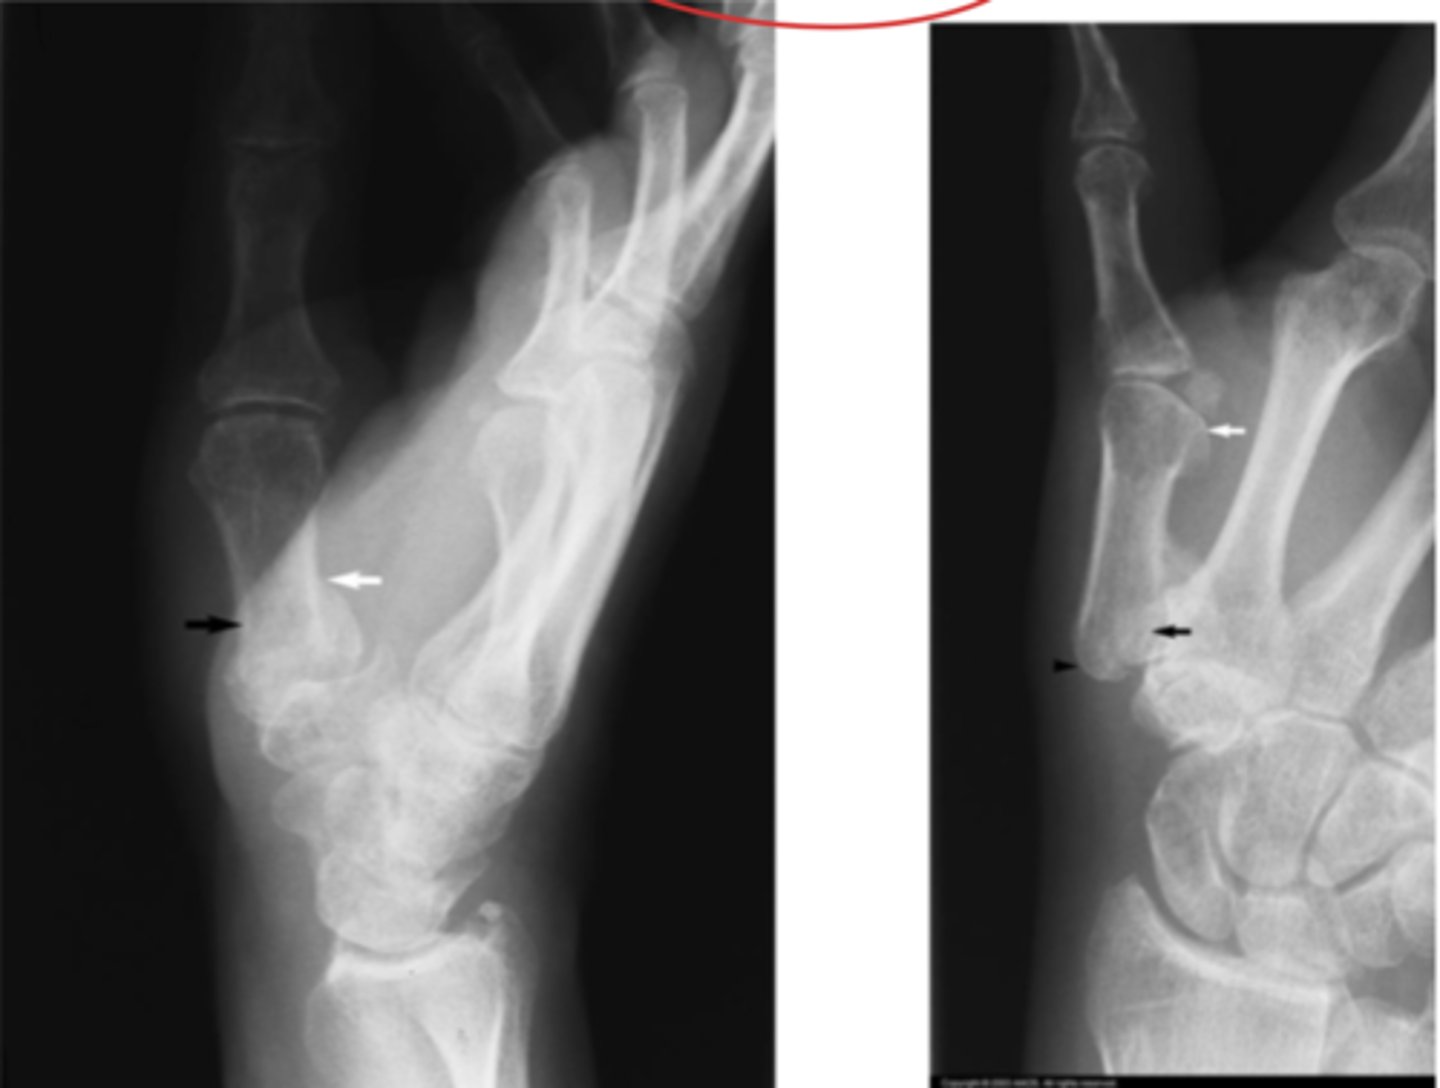

DISI

What is the issue?

Lunate instability

Perilunate instability

Terry Thomas sign (DISI)